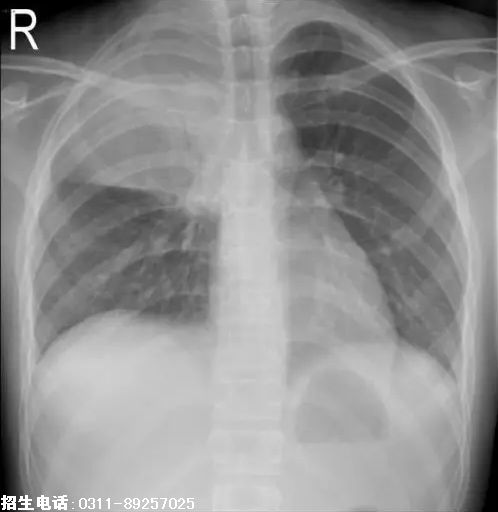

4、题干:男,10岁。发热、咳嗽6天。结合X线片,此诊断为

答案:C

解析:大叶性肺炎表现为肺透亮度轻度下降或密度稍高的模糊影,均匀的致密影。肺炎累及整个肺叶时,以叶间裂为界,边缘清楚,形态与肺叶一致。(C对)